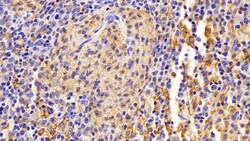

Ionized calcium-binding adapter molecule 1 (IBA1), also known by its gene name AIF1, is a protein expressed predominantly by microglia in the brain and spinal cord. This protein belongs to the EF-hand calcium-binding protein family and plays a crucial role in microglial activation and migration in response to brain injury or neuroinflammation. IBA1's function is integral to microglial motility and phagocytic activity, facilitating the cellular response to pathogenic stimuli and promoting tissue homeostasis and repair in the central nervous system. IBA1 serves as a reliable marker for activated microglia in various neurological disorders, including Alzheimer's disease, Parkinson's disease, and multiple sclerosis, where increased expression correlates with disease progression and severity. The protein's structural features enable it to bind calcium ions, inducing conformational changes that activate signaling pathways essential for microglial function. Its expression is highly regulated by inflammatory cytokines, underpinning its role in neuroimmune responses. Due to its specific expression in microglia during pathological conditions, IBA1 is widely used in research as a marker to study microglial status and activity, and it remains a focal point for understanding microglial involvement in neurodegenerative diseases.Specifications

| Immunohistochemistry (Paraffin), Western Blot | |